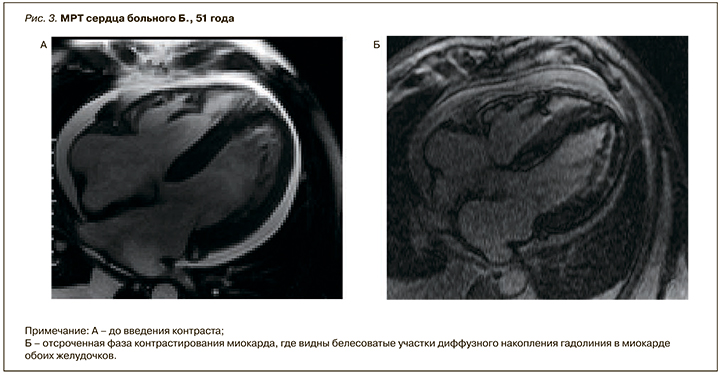

Таким образом, жалобы, данные объективного и инструментального обследования свидетельствовали о том, что у больного Б., 51 года, имеет место ХСН с низкой ФВ (ФВ=29%). Данные ЭхоКГ указывали на значительную концентрическую гипертрофию ЛЖ с нарушением диастолической функции III степени при отсутствии артериальной гипертензии или любого другого кардиологического заболевания в анамнезе. С учетом выявленных изменений по данным ЭхоКГ необходимо было исключить генетические аномалии сердца, в первую очередь рестриктивную кардиомиопатию и инфильтративные заболевания сердца. В таких ситуациях для уточнения характера поражения сердца рекомендуется МРТ.

Данные МРТ сердца с гадолинием: отмечается симметричная гипертрофия миокарда ЛЖ, толщина МЖП в средней трети – 19 мм, толщина миокарда верхушки – 7 мм, толщина задней стенки ЛЖ – 15 мм. Сократимость миокарда ЛЖ значительно снижена за счет гипокинеза всех стенок (ФВ – 15%). Признаков обструкции полости ЛЖ, выносящего тракта ЛЖ нет. В верхней трети МЖП определялись клефты шириной основания 5 мм, глубиной до 9 мм. После внутривенного введения контрастного препарата в отсроченную фазу (через 10 мин) было обнаружено диффузное контрастирование миокарда ЛЖ, межпредсердной перегородки и правого желудочка, более выраженное по переднебоковой стенке, в МЖП со стороны правого желудочка. Описанная картина наиболее характерна для амилоидоза сердца (рис. 3).